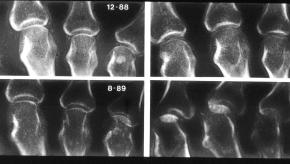

Denosumab Protects Against RA Erosions

Combining denosumab (Prolia) with a conventional disease-modifying antirheumatic drug (DMARD) such as methotrexate showed promise for slowing radiographic damage in rheumatoid arthritis (RA), a manufacturer-sponsored phase III trial called DESIRABLE found.